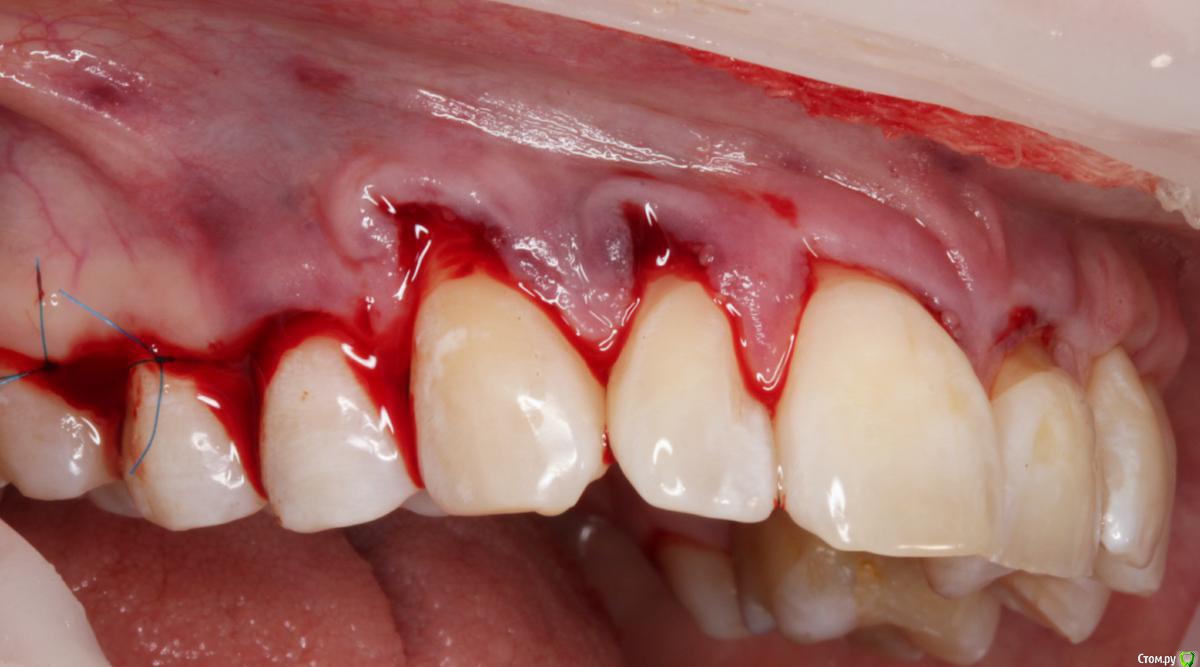

Dmitry DK Опубликовано 31 августа, 2019 Поделиться Опубликовано 31 августа, 2019 Доброго дня! Первичное обращение пациентки было связано с отсутствием 25 зуба, эстетические нарушения слизистой, клиновидные деф-ты в области других зубов - не смущали.В итоге решили, раз проводим операцию ( импл + ССТ ), закроем попутно и рец на верхней челюсти.Реставрацию на 21 зуб все не ставит... Приятных тебе выходных! ) Пациентка проходила лечение 2,5 года назад, пришла на проф осмотр 7 Ссылка на комментарий

Dman Опубликовано 2 сентября, 2019 Поделиться Опубликовано 2 сентября, 2019 ничего себе попутно, в итоге на имплант 15 минут, а на рецессии 2 часа?)) Ссылка на комментарий

Dmitry DK Опубликовано 2 сентября, 2019 Автор Поделиться Опубликовано 2 сентября, 2019 ничего себе попутно, в итоге на имплант 15 минут, а на рецессии 2 часа?))У меня те же мысли были), но согласитесь, что если бы мы этого не сделали - разница в зенитах былабы слишком велика Ссылка на комментарий